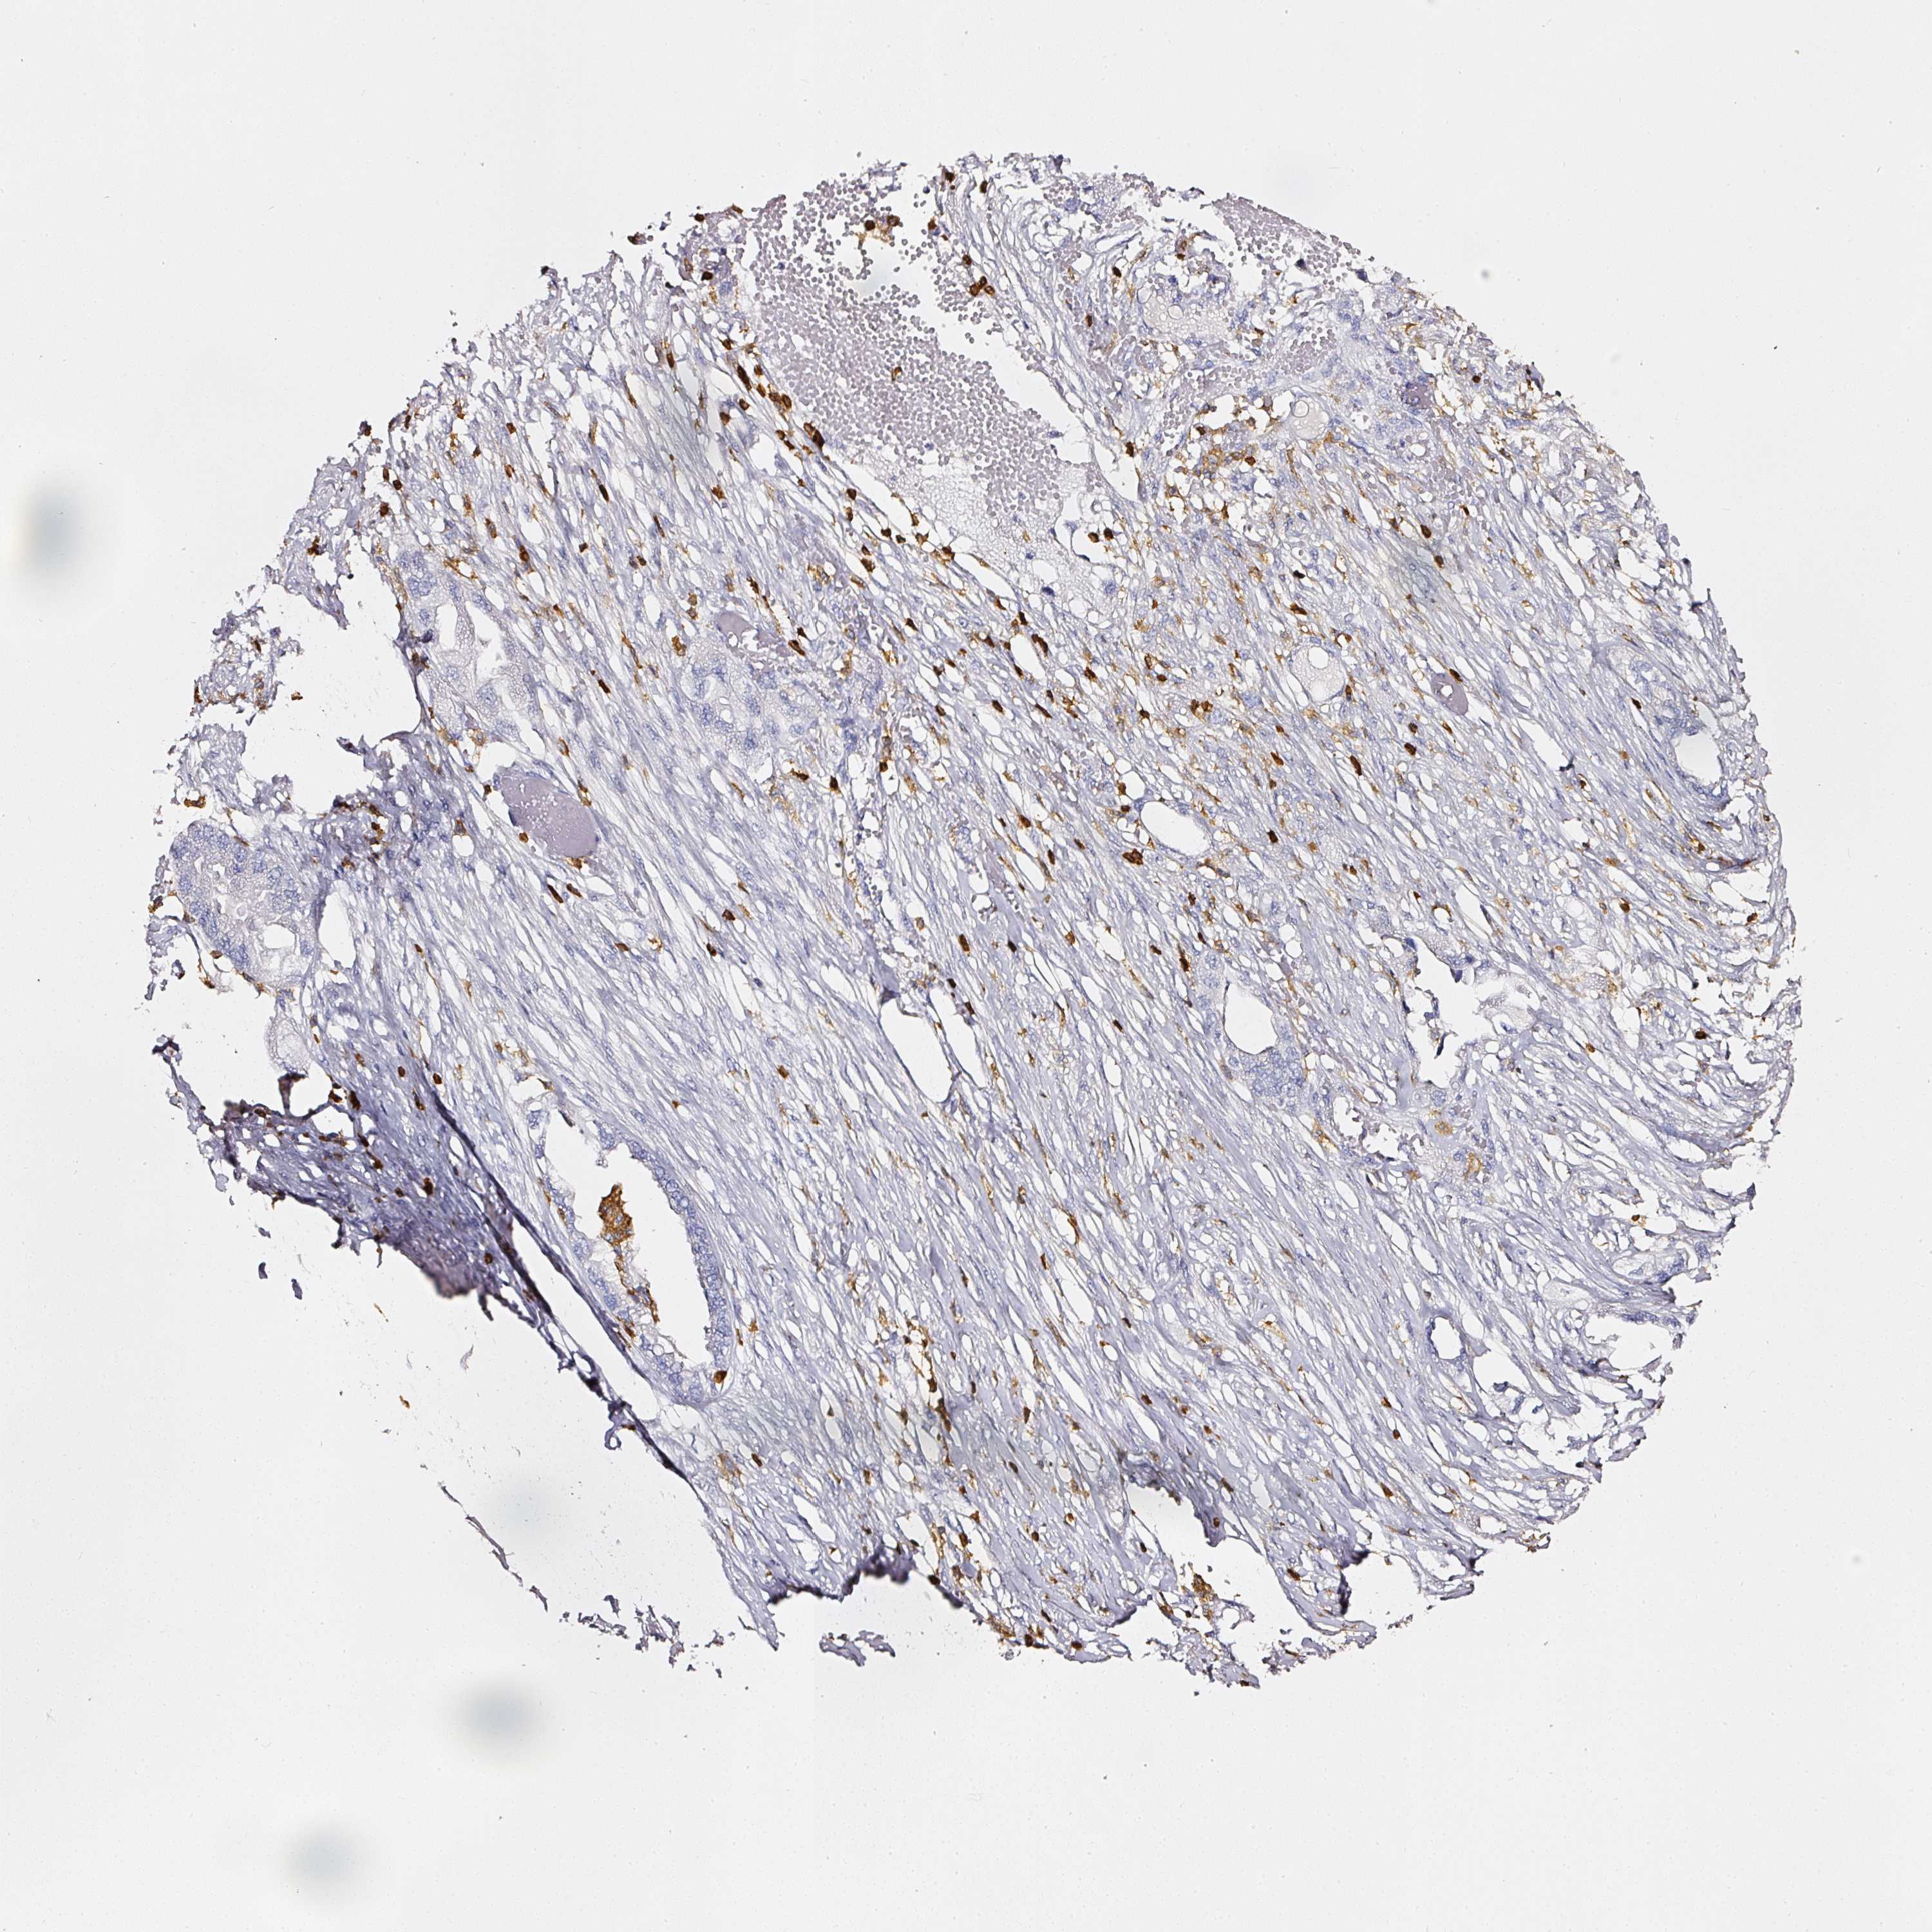

ENDOMETRIAL CANCER - Protein expressioni

A mouse-over function shows sample information and annotation data. Click on an image to view it in a full screen mode. Samples can be filtered based on level of antibody staining by selecting one or several of the following categories: high, medium, low and not detected. The assay and annotation is described here.

Note that samples used for immunohistochemistry by the Human Protein Atlas do not correspond to samples in the TCGA dataset.

Antibody stainingi

Antibody staining in the annotated cell types in the current human tissue is reported as not detected, low, medium, or high, based on conventional immunohistochemistry profiling in selected tissues. This score is based on the combination of the staining intensity and fraction of stained cells.

Each image is clickable and will lead to virtual microscopy that enables deeper exploration of all samples and also displays staining intensity scores, fraction scores and subcellular localization as well as patient and tissue information for each sample.

Antibody HPA018849

Antibody HPA019536

Antibody CAB033987